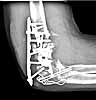

At surgery it appeared infected. Cultures eventually grew out strep viridans subcultured through broth. It was very hyperemic. I treated it with hardware removal, a spanning plate that was meant to provide temporary stability, and irrigation & debridement x 2. (I did not use an external fixator because of the osteoporosis, and the inability to get stability of the fragments.) An antibiotic impregnated cement spacer was added. Files( after I&D.) Last I&D was in March 2004.

after I&D